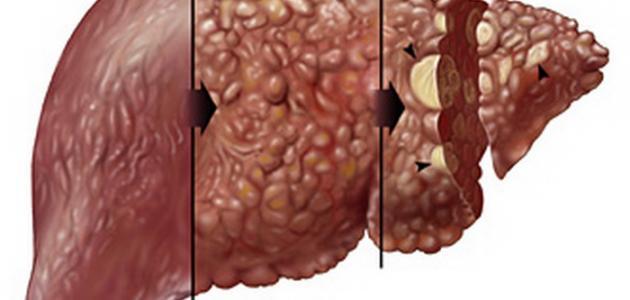

تليف الكبد

تليف الكبد، المعروف أيضًا بتشمع الكبد، هو حالة مرضية تؤثر على الأنسجة المكونة للكبد، مما يؤدي إلى تكوين ألياف ضارة تحل محل الأنسجة السليمة. على المدى الطويل، يمكن أن يؤدي ذلك إلى توقف الكبد عن أداء وظائفه بشكل صحيح. قد يتسبب تليف الكبد في تضخم حجم الكبد أو تقليصه، مما يعرف بضمور الكبد. من الوظائف الأساسية للكبد أنه يخلص الجسم من السموم، وعندما يحدث تليف، تتراكم هذه السموم والسوائل في البطن، مما قد يؤدي إلى تسمم الجسم والوفاة في بعض الحالات. كما أن للكبد دورًا مهمًا في إنتاج مواد تخثر الدم، مما يساعد في تقليل النزيف الناتج عن الجروح.

للتقليل من الأضرار التي تلحق بالكبد، يجب على المرضى اتباع نظام غذائي متوازن وغني بالصوديوم، والتأكد من أن اللقاحات سارية المفعول، وتجنب تناول أي دواء دون استشارة الطبيب. من الضروري أيضًا تقليل استهلاك المشروبات الكحولية. يمكن أن يساعد إجراء الفحوصات الطبية المبكرة في تحديد أسباب المرض، مما يجعل العلاج أكثر فعالية. من الأمراض المرتبطة بالكبد تضخم الأوردة وسرطان الكبد، وفي حال تفشي تليف الكبد، قد تصبح زراعة الكبد ضرورة ملحة. بعد موافقة الطبيب، تُجرى الفحوص اللازمة لتحديد قدرة المريض على قبول عملية الزراعة.